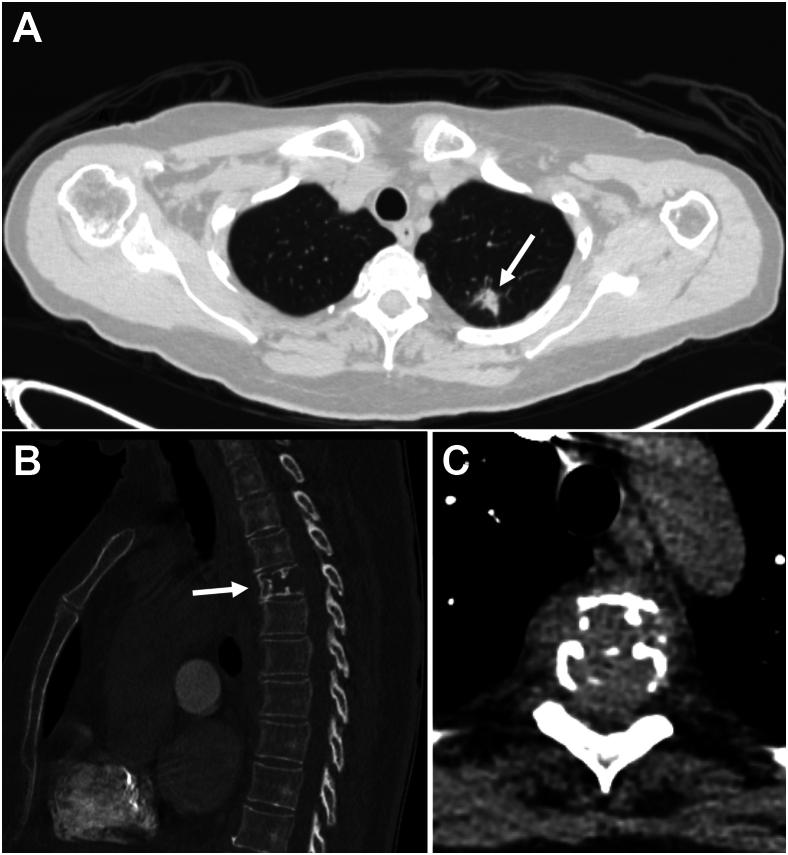

Vertebral hemangiomas (VHs) are common, benign angiomatous lesions of the spine with an incidence rate of 10% to 12% in the population. VHs have a characteristic appearance on imaging; however, a subset demonstrate atypical features that resemble more sinister pathologic processes, such as malignant neoplasms or metastatic disease. We report a case of an atypical VH that was initially thought to be a metastasis in a 75-year-old patient with a newly diagnosed pulmonary nodule. Our goal is to highlight the key findings of VHs on various imaging modalities that can potentially help minimize unnecessary investigations or interventions.

椎体血管瘤(VHs)是脊柱常见的良性血管瘤病变,在人群中的发病率为10%至12%。VHs在影像学上有特征性表现;然而,一部分显示出非典型特征,类似于更凶险的病理过程,如恶性肿瘤或转移性疾病。我们报告一例非典型VH病例,该病例最初被认为是一名75岁新诊断为肺结节患者的转移瘤。我们的目的是强调VHs在各种影像学检查中的关键表现,这可能有助于尽量减少不必要的检查或干预。